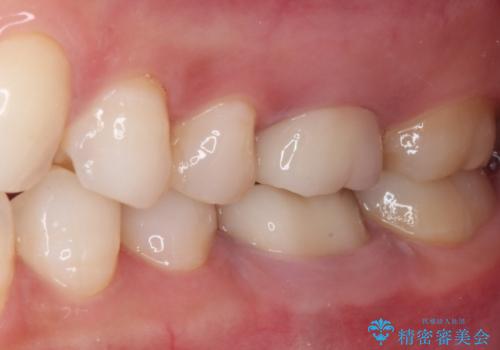

口腔内から、土台も含め銀歯がなくなったことでメタルフリーとなりました。